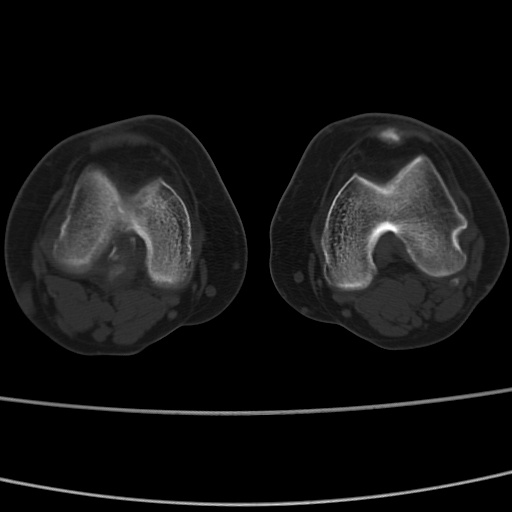

女性,50岁。【请提供患者临床症状体征】

右膝关节退行性改变,关节游离鼠。

右膝关节退行性改变,滑膜黏液囊钙/骨化并游离。

右膝关节退行性改变